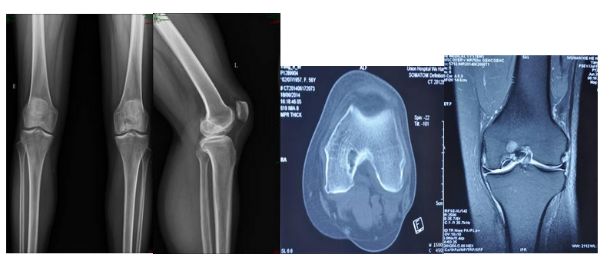

患者楊女士,3年前開始出現(xiàn)左膝關(guān)節(jié)疼痛,不能上下樓梯,疼痛難忍,日?;顒?dòng)受到限制,診斷為“左膝關(guān)節(jié)骨關(guān)節(jié)炎”,就診于省級(jí)知名骨科專家、邦爾骨科集團(tuán)首席專家、嘉興邦爾骨科醫(yī)院院長(zhǎng)趙凱教授專家門診。經(jīng)趙凱教授為其診查后,發(fā)現(xiàn)患者膝關(guān)節(jié)病變局限于內(nèi)側(cè)髁,非常適合做“微創(chuàng)單髁膝關(guān)節(jié)置換術(shù)”,并且手術(shù)創(chuàng)傷小,術(shù)中無出血,術(shù)后恢復(fù)快。手術(shù)過程很順利,術(shù)后第5天患者不用拄拐就可下床活動(dòng),回歸到正常生活。

這種微創(chuàng)膝關(guān)節(jié)置換,相比于傳統(tǒng)膝關(guān)節(jié)置換手術(shù),術(shù)中無出血,感染率低,術(shù)后恢復(fù)更快,無皮下淤血瘀斑,膝關(guān)節(jié)活動(dòng)度更加良好。

術(shù)前檢查顯示患者左側(cè)膝關(guān)節(jié)骨性關(guān)節(jié)炎,病變僅限于內(nèi)側(cè)髁

術(shù)后顯示假體位置良好